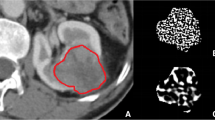

CT images were reviewed, and the maximum tumor diameter was recorded at a picture archiving and communications system (PACS) workstation (Synapse, Fujifilm Medical Systems) by a radiologist with 15 years of experience in body imaging (YD), blinded to pathology. The axial-enhanced CT image of the largest tumor cross section was identified, anonymized, and exported to a Digital Imaging and Communications in Medicine (DICOM) file. The DICOM files were uploaded to a cloud server with the TexRAD CTTA software (version 3.9, TexRAD Ltd.). A region of interest (ROI) was drawn to include the entire tumor (Fig. 2). The solid lesion algorithm was implemented which included only pixels above – 50 HU within the ROI using “threshold” as padding (erosion scale = 0) for reducing edge artifact.

CT texture analysis of ccRCC. a Delineation of tumor (blue line). b–d Color texture overlays of tumor outlined by ROI at fine (b), medium (c), and coarse (d) spatial filters. These images undergo pixel-by-pixel histogram analysis to yield CTTA parameters. When a fine spatial filter is applied, the internal structure of the tumor can be clearly seen

CTTA methodology using the filtration-histogram technique has been described elsewhere [13, 21,22,23]. Once ROIs are obtained, the CTTA software modifies the pixel data using several Laplacian spatial scaling factors (SSF), which extracts and enhances features of different sizes (mm) ranging from fine (SSF = 2 mm), medium (SSF = 4 mm), and coarse (SSF = 6 mm) texture scales. A fine filter tends to enhance tissue parenchymal features, while medium to coarse filters enhance vascular features [24]. The filtration step derives filtered maps, which are quantified to yield four parameters by histogram and statistical analysis. These parameters were mean value of positive pixels (average brightness considering only the positive pixel values), entropy (heterogeneity of pixel intensities), kurtosis (peakedness or sharpness of the pixel distribution), and skewness (asymmetry of pixel distribution). The mathematical process of calculating these parameters has been previously described [15, 25, 26].